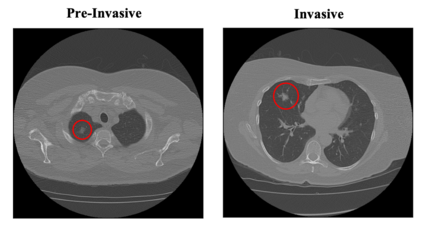

Lung cancer is the leading cause of mortality from cancer worldwide and has various histologic types, among which Lung Adenocarcinoma (LUAC) has recently been the most prevalent. Lung adenocarcinomas are classified as pre invasive, minimally invasive, and invasive adenocarcinomas. Timely and accurate knowledge of the invasiveness of lung nodules leads to a proper treatment plan and reduces the risk of unnecessary or late surgeries. Currently, the primary imaging modality to assess and predict the invasiveness of LUACs is the chest CT. The results based on CT images, however, are subjective and suffer from a low accuracy compared to the ground truth pathological reviews provided after surgical resections. In this paper, a predictive transformer-based framework, referred to as the "CAE-Transformer", is developed to classify LUACs. The CAE-Transformer utilizes a Convolutional Auto-Encoder (CAE) to automatically extract informative features from CT slices, which are then fed to a modified transformer model to capture global inter-slice relations. Experimental results on our in-house dataset of 114 pathologically proven Sub Solid Nodules (SSNs) demonstrate the superiority of the CAE-Transformer over the histogram/radiomics-based models and its deep learning-based counterparts, achieving an accuracy of 87.73%, sensitivity of 88.67%, specificity of 86.33%, and AUC of 0.913, using a 10-fold cross-validation.